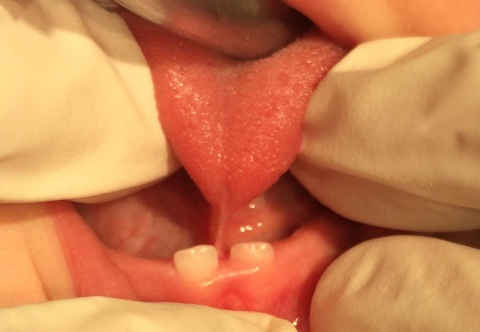

Type 1 Ankyloglossia